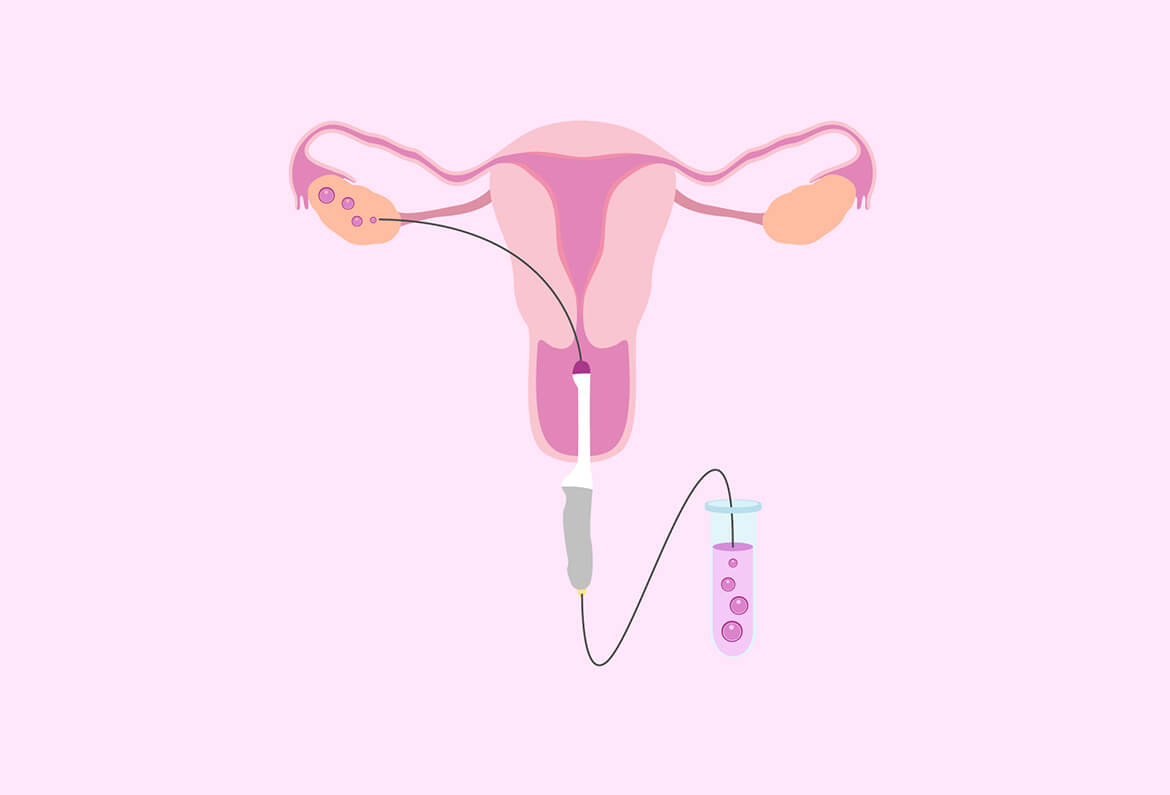

Step 4: The Big Day—Egg Retrieval

What Happens?

Now it’s showtime! Egg retrieval is a quick procedure (about 10-20 minutes) done under sedation. Here’s the play-by-play:

- You’re hooked up to an IV with sleepy meds—think twilight nap, not full-on surgery vibes.

- The doctor uses an ultrasound wand (yep, back in the vagina) to spot your follicles.

- A thin needle goes through the vaginal wall into each follicle, sucking out the fluid—and the eggs—with a tiny vacuum.

- The eggs get whisked off to the lab while you snooze.

The Wow Factor

That needle? It’s guided by ultrasound, so it’s super precise—like a video game where the prize is your future kiddo. And get this: the whole thing’s over before you even realize it started!